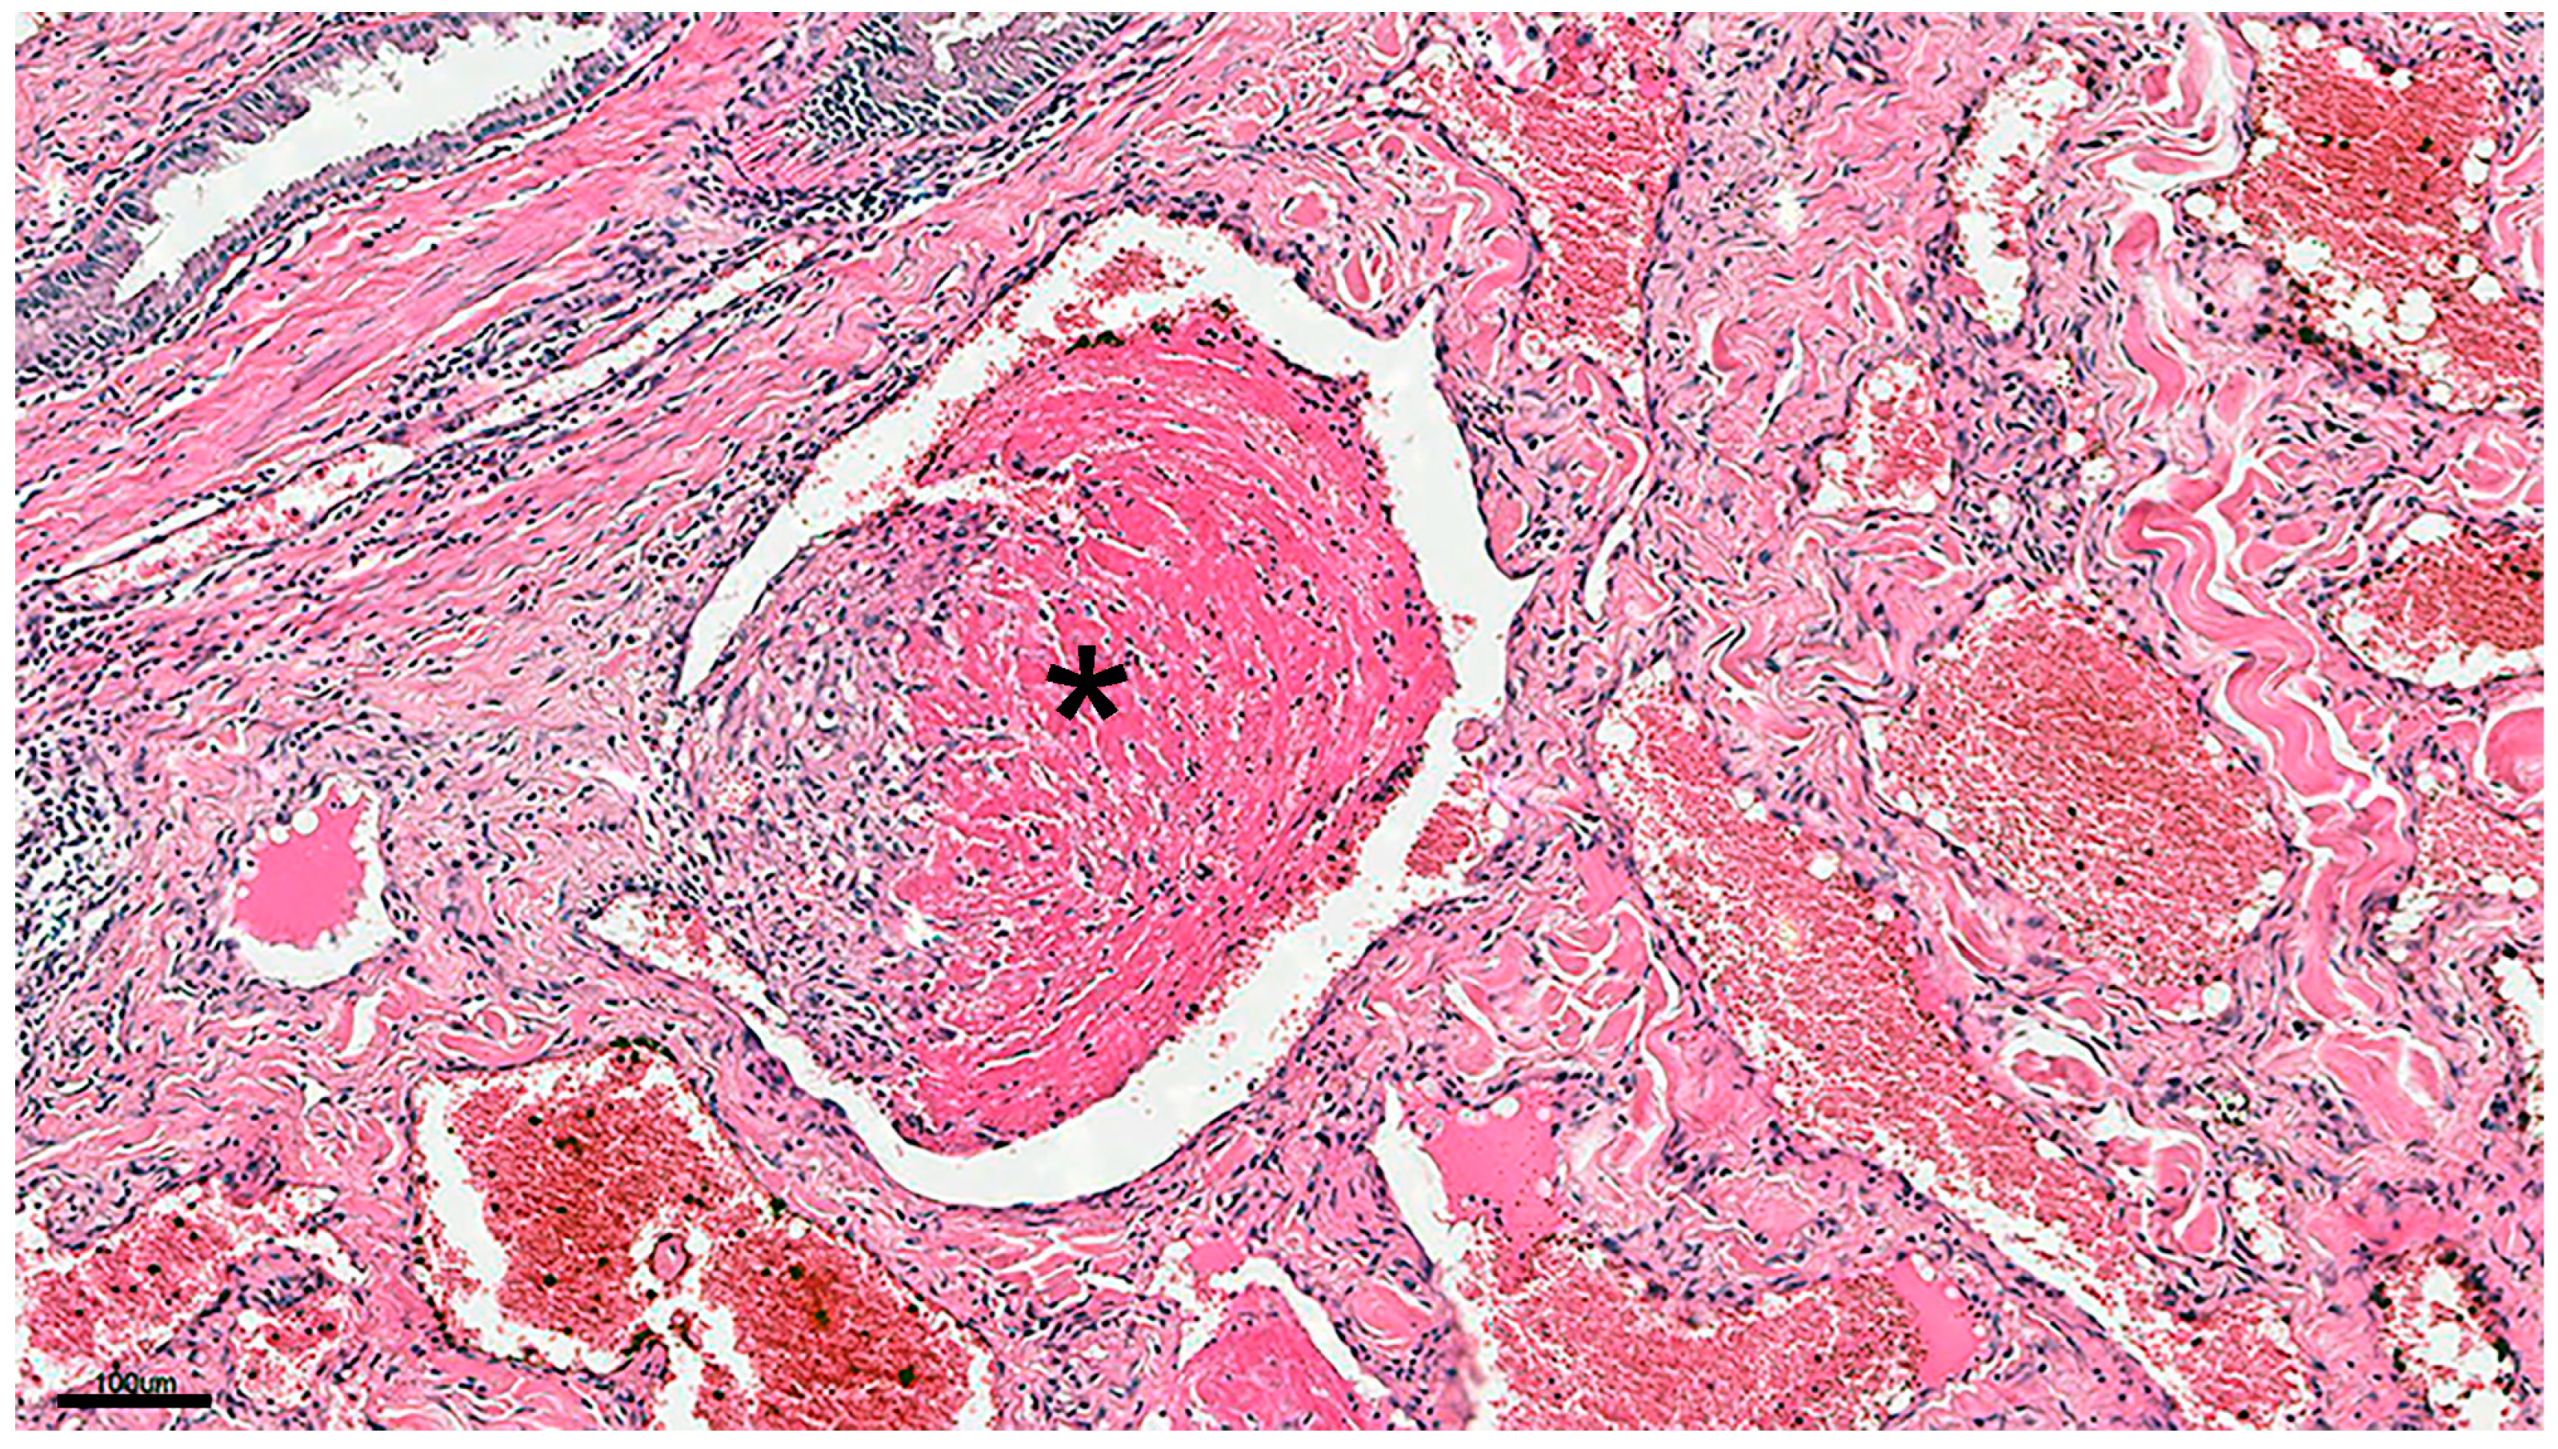

Tumor cells forming blood vessels were lined with a single layer of neoplastic cells with normochromic nuclei, and mitotic figures were rare. Thrombosis was observed in 12 cases, with some thrombi organized (Figure 3).

Figure 3.

Organized thrombi in mixed cutaneous hemangioma (asterisk). H&E ×100. Scale = 100 µm.

For hemangiomas, the mean age was >8 years old [3,16]. In our diagnosed hemangioma cases, the average age of the dogs at the time of excision was 8.36 ± 2.08 years; therefore, there is a difference in the average age of dogs reported in previous studies compared with our study [3]. In contrast, it has been reported that tumors had already developed at birth and during the first few years of life, suggesting a type of vascular malformation [3]. As the dogs in this study were diagnosed over 5 years old, hemangiomas due to vascular malformations were unlikely. There are contradictory reports regarding sex; some argue that there are no differences between the two sexes, whereas others propose that hemangiomas are more frequent in females than in males [3], and vice versa [16]. In our study, no sex predilection was observed. In addition, dogs with short-hair coats and lightly pigmented skin have been proposed to be more susceptible to hemangiomas and hemangiosarcomas than those with variable-length hair coats or pigmentation [3,15]. In our study, hemangiomas and hemangiosarcomas were detected in long-haired dogs of multiple breeds. Chronic solar damage has been suggested to be a cause of dermal hemangiomas [1,2,3]. Therefore, we could not establish a clear relationship between skin vascular tumors and ultraviolet light exposure. However, hemangiomas were found just below the epidermis in 8 of the 25 dogs, indicating a relationship between skin hemangiomas and solar damage, at least in these 8 cases. Further research is required to determine the relationship between dog breed and solar damage in Uruguay. The present morphological changes in hemangiomas were similar to those previously reported [3,16,36]. In this study, the formation of multiple organized thrombi was considered one of the characteristic changes. More research is required to determine the pathogeny of thrombi formation in canine cutaneous hemangiomas. The large number of organized thrombi may be related to blood flow in the tumor and the time course from tumor formation. The present study also shows that the mixed type was more common, as mentioned in the Results Section and reported previously [3]. Depending on the time from the onset of the tumor and the condition of the dog, tumors may be complicated, comprising both capillary and cavernous types, with proliferation of the connective tissue. Immunohistochemical studies have reported that factor VIII-related antigen staining is more sensitive in canine hemangiomas [37], and that CD31 markers have limited diagnostic relevance for vascular neoplasms in cats [32] but high diagnostic relevance in hemangiomas and hemangiosarcomas in dogs [38]. In our cases, the tumor cells in dogs were immunoreactive against both CD31 and factor VIII-related antigen primary antibodies, confirming their combined use as biomarkers of canine cutaneous vascular tumors.